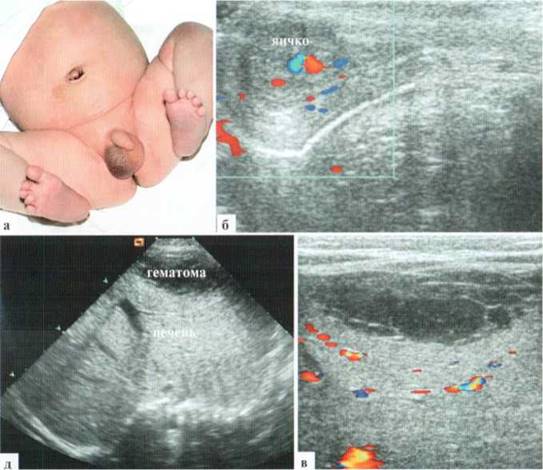

Гематоцеле у детей встречается нечасто и в большинстве случаев, является не следствием травмы мошонки, а появляется при скоплении крови в брюшной полости, откуда через необлитерированный вагинальный отросток брюшины кровь поступает в мошонку. Наблюдается гематоцеле преимущественно у новорожденных на фоне интранаталь- ной травмы не только паренхиматозных органов брюшной полости, но и кровоизлияний в надпочечники, а также при нарушениях свертывания крови. Клинические проявления сводятся к СОМ, при этом характерно появление багрово-цианотичной окраски половины мошонки на стороне поражения или — всей мошонки при билатеральном поражении. Пропальпировать яички и клинически оценить их состояние практически невозможно. Лечение гематоцеле в большинстве случаев консервативное и проводится параллельно лечению основного заболевания. При значительном напряжении возможна пункция оболочек яичка и эвакуация содержимого.

На УЗИ, в отличие от гидроцеле, кровь в оболочках выглядит как содержимое средней эхогенности, при исследовании высокочастотными датчиками — как мелкодисперсная взвесь. Иногда на поверхности яичка определяются фиксированные к нему сгустки крови в виде нежного «облака» средней эхогенности с неровными краями. Собственно яичко при изолированном гематоцеле не изменяется, сосудистый рисунок в нем сохранен, однако его визуализация у детей раннего возраста возможна не всегда (2.7.5).

Рис. 2.7.5. Гидроцеле и гематоцеле у младенцев:

а, б — гидроцеле. Содержимое оболочек анэхогенное без включений, сосудистый рисунок в яичке сохранен;

в, г — гематоцеле. Содержимое оболочек выглядит как мелкодисперсная взвесь (линейный датчик 12 М Гц), на поверхности яичка (конуры показаны пунктирной линией) фиксированы сгустки крови неправильной формы, средней эхогенности (стрелки), сосудистый рисунок в яичке сохранен

Как уже говорилось, гематоцеле у детей (преимущественно раннего возраста) может быть не самостоятельным заболеванием, а симптомом гемоперитонеума. Об этом обстоятельстве необходимо всегда помнить и при малейшем сомнении расширять зону обследования (рис. 2.7.6). В первую очередь внимание должно быть обращено на содержимое свободной брюшной полости (скопление содержимого, в первую очередь, в полости малого таза, в латеральных каналах) и состояние паренхиматозных органов (печень, селезенка, почки, надпочечники).

Рис. 2.7.6. Гематоцеле у младенца с разрывом печени. Глубоко недоношенный ребенок поступил на 3-й сутки жизни с подозрением на антенатальный перекрут правого яичка. Общее состояние очень тяжелое за счет полиорганной недостаточности. Объективно: правая половина мошонки багрово-цианотичного цвета, значительно увеличена в размерах. Других локальных изменений не выявлено:

а, б — правое яичко сохранено, в оболочках много содержимого в виде мелкодисперсной взвеси с тонкими септами, подозрительного на кровь; в — аналогичное по структуре содержимое в полости малого таза за мочевым пузырем;

г — жидкость в небольшом количестве вокруг правой доли печени;

д, е — массивное повреждение печени (центральная гематома — между стрелками).

Размер собственно дефекта паренхимы — около 3 см в диаметре

На фоне консервативного лечения ребенок выздоровел, катамнез в течении 5 лет — мальчик здоров.